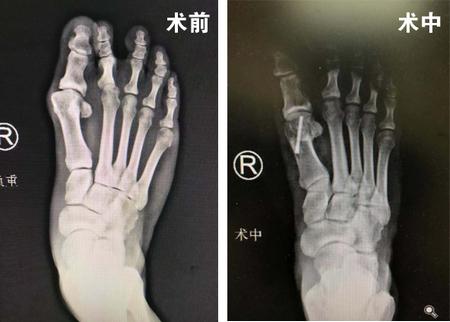

7月11日,刘大姐来到足踝外科专家门诊,找到了足踝科大科主任、副院长石荣剑。石院长安排刘大姐做完体检和相关影像检查后,确诊刘大姐为先天性右足踇外翻畸形,决定为患者实施微创踇外翻矫正术。

石院长又给患者介绍,微创踇外翻矫正术采用韩国进口低频超声微磨锯,切口很小无需缝合;4毫米微磨锯锋利、精准、自带注水降温,更好地保护骨骼血运,从而使得截骨处更快愈合。

很快,石院长为患者进行了右足踇外翻矫形术。麻醉师采用超声引导下神经阻滞,石院长周吉医生通过不到一厘米切口,在第1跖趾关节胫侧利用4毫米进口超声磨锯微创截骨,1个多小时,再次完美修整踇外翻。